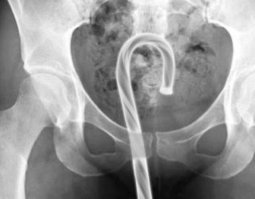

Используя секс-игрушки, помните: они тоже могут застрять внутри!

0